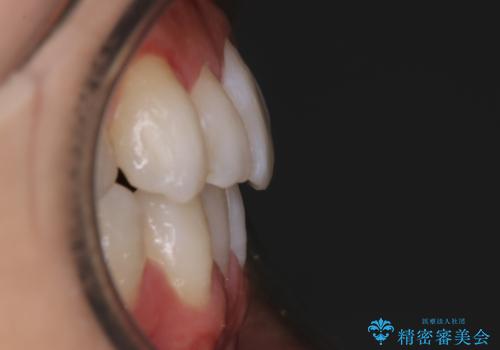

【非抜歯】八重歯を治す マウスピース矯正

- 前歯のガタつきの治療を主訴にご来院されました。

目立たない装置をとのご要望があったため、検査結果をふまえてインビザラインでの非抜歯矯正を行うこととなりました。

非抜歯での治療

抜歯をせずに歯のガタつきを治すためのスペースを作るために

①歯の遠心移動

②歯列弓の拡大

③IPR(歯を少し小さく削る)

この3つの方法を複合的に組み合わせて治療を行いました。

抜歯をせずとも笑った時の歯の見え方が劇的に変化していることが分かります。